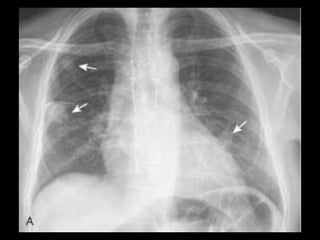

Sequestro intralobar com infecções recorrentes

Sequestro pulmonar Definição:segmento de tecido pulmonar que é separado da árvore brônquica e recebe seu suprimento sanguíneo de uma artéria sistêmica; Dois tipos: intralobar e extralobar; A maioria dos sequestros são tipo intralobar; O suprimento vascular em 80-90% dos casos provêm da artéria aorta descendente; Complicações: hemoptise e BCP repetição; Diagnóstico: identificação do vaso anômalo.

Sequestro intralobar cominfecções recorrentes